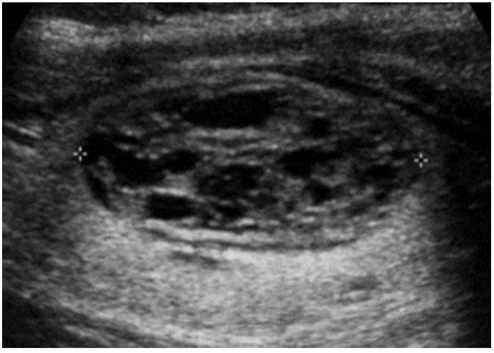

Paciente do sexo masculino, 38 anos, notou assimetria de volume na região anterior do pescoço à palpação e procurou seu médico, o qual solicitou ultrassonografia da região cervical. A única alteração encontrada foi o nódulo tireoideano abaixo.

De acordo com o ACR Thyroid Imaging, Reporting and Data System (TI-RADS), assinale a alternativa que contém a recomendação correta para o caso acima.